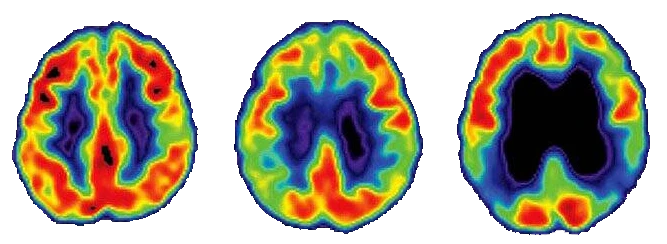

Yaygın görülen bir demans türü olan Alzheimer, beyin hücrelerinin yok olmasına neden olan ilerleyici bir nörolojik hastalıktır. Hastalık çoğunlukla 65 yaş ve üzerindeki bireyleri etkilese de daha genç başlangıçlı örneklerine de sıklıkla rastlanması nedeniyle bir yaşlılık dönemi hastalığı olarak nitelendirilmesi doğru bir tanım değildir.

Alzheimer, başlangıç, orta ve ileri olmak üzere 3 evrede incelenir. Alzheimer hastalığının başlangıç evresinde kişi de hafif derecede unutkanlıklar meydana gelse de kişi bu durumu tolere edebilir. Orta dönemde, Alzheimer hastalığının en uzun evresi olarak kabul edilir. Hastalığın belirtilerinin daha belirgin olarak hissedildiği bu dönemde kişi, düşüncelerini ifade etme konusunda zorluklar yaşar. İleri dönem Alzheimer hastalığında hastanın her konuda bakıma ihtiyaç duyar. Hasta bu evrede tüm farkındalığını kaybederek iletişim kurma konusunda sıkıntı yaşar ve fiziksel eylemlerini tek başına yapamaz.